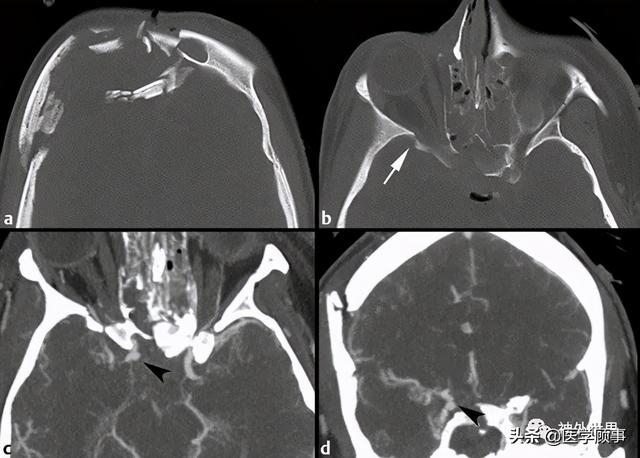

掌握颅底骨性解剖和常见骨折,脑脊液漏影像诊断

最全的颅骨ct解剖及外伤骨折的诊断